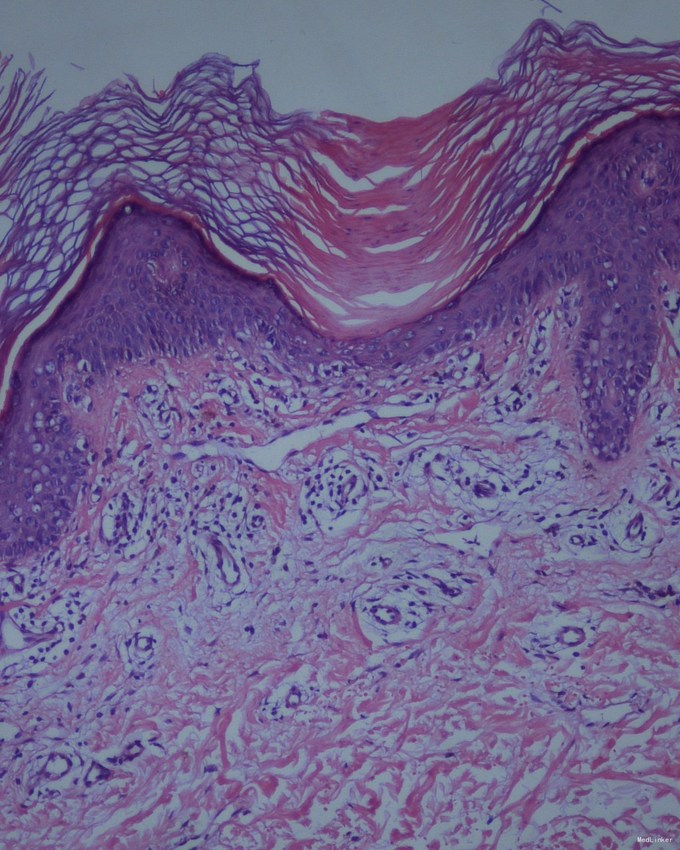

查体:右下肢自臀部自足背外侧,线状分布褐色角化丘疹,融合。 病理:取角化隆起的部位做检查,可见特征性的改变。在角质层内有一楔形的鸡眼样板,它是一个由角化不全细胞所组成的细胞柱,在鸡眼样板下方的颗粒层减少或消失,棘细胞层内有胞浆嗜酸性染、核深染的角化不良细胞。